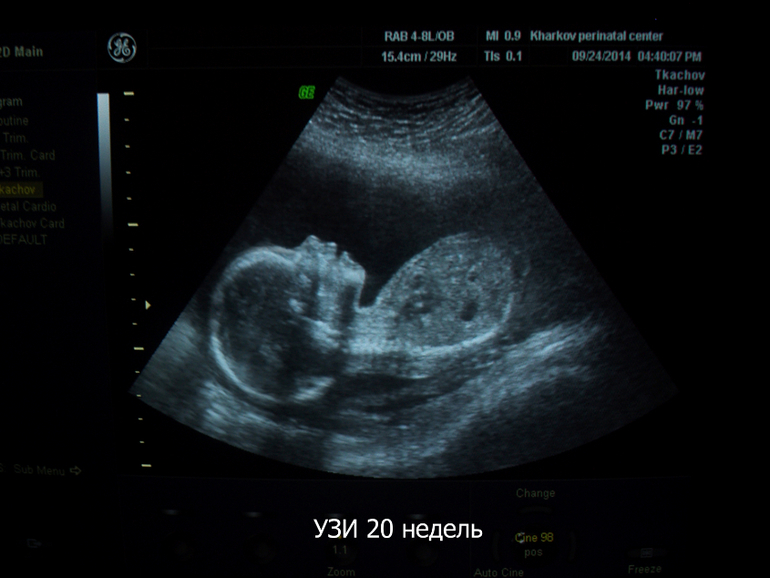

Мое узи в перинатальном в 13 и 20 нед